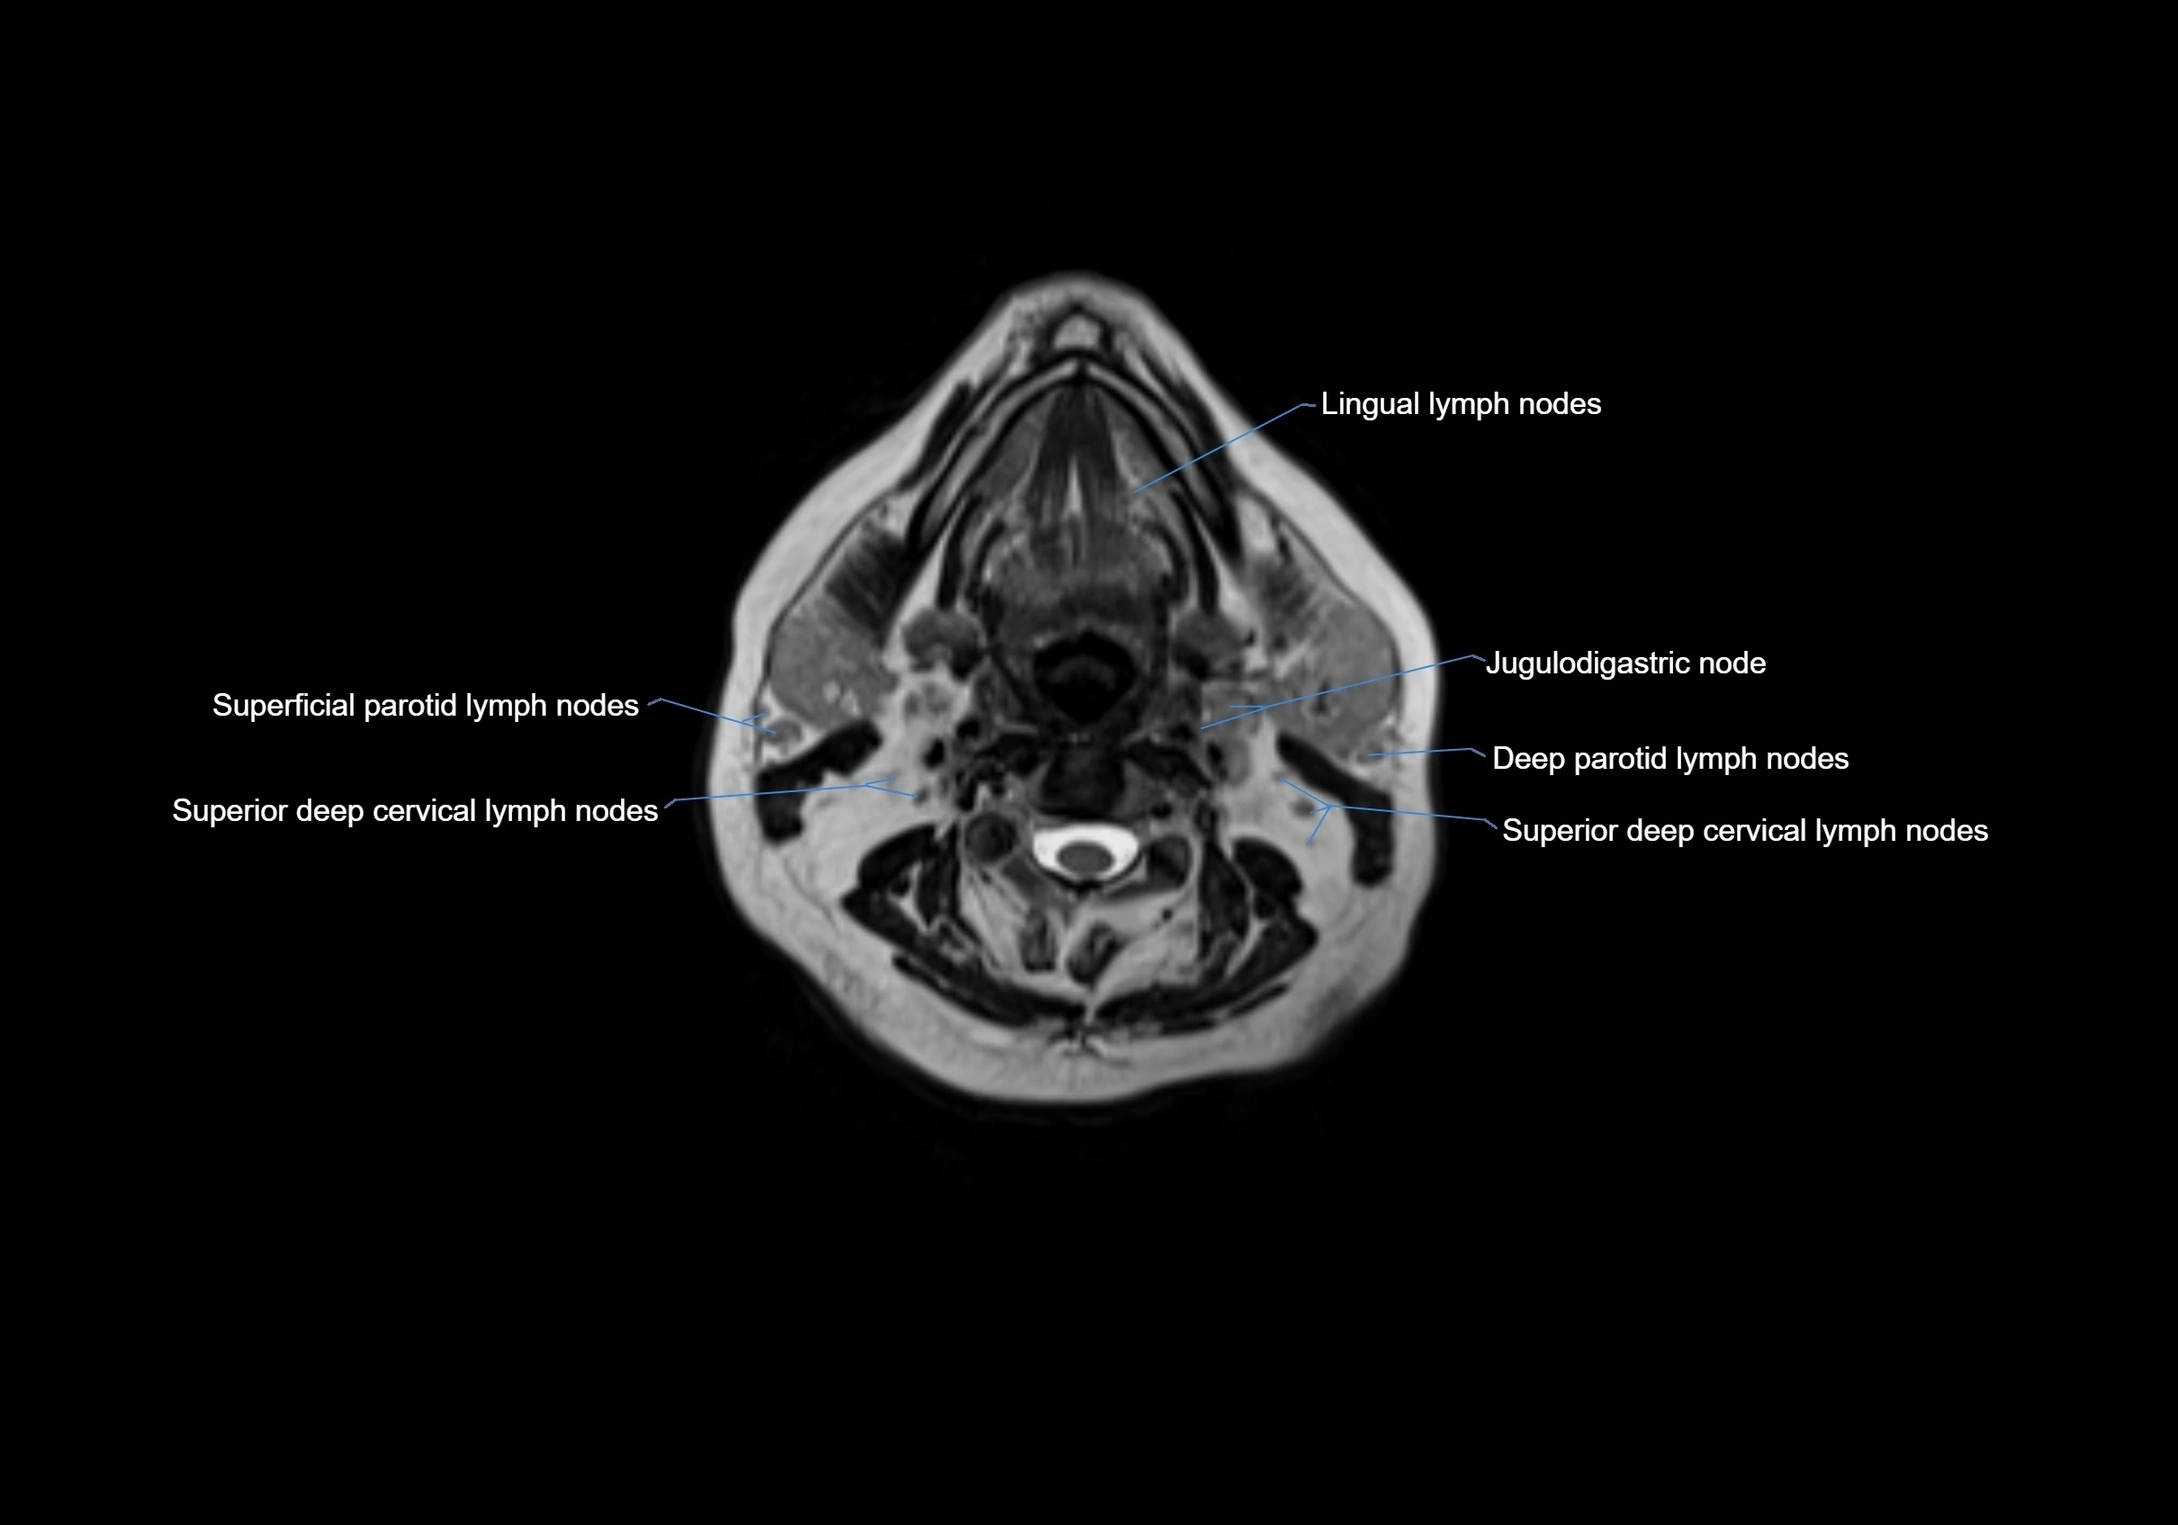

Accessory lymph nodes

Accessory lymph nodes are small, secondary lymph nodes located along the main facial and cervical lymphatic chains, often adjacent to primary lymph nodes, such as preauricular, submandibular, or occipital nodes. They are typically less than 5 mm in diameter, embedded within subcutaneous fat or connective tissue, and may be variable in number and location. These nodes provide additional filtration and immune surveillance for lymph collected from the face, scalp, and neck regions. Accessory lymph nodes are usually non-palpable in healthy individuals but may enlarge in response to infection, inflammation, or metastasis, making them clinically significant.

Location

• Found along primary lymph node chains, including preauricular, submandibular, parotid, and occipital regions

• Embedded in subcutaneous fat or superficial fascia, often lateral or posterior to primary nodes

• Variable in number; may occur unilaterally or bilaterally, depending on individual anatomy

MRI Appearance

T1-weighted images:

• Normal accessory nodes appear as small, oval hypointense to intermediate signal structures within subcutaneous fat

• Surrounded by hyperintense fat, enhancing contrast for visualization

T2-weighted images:

• Nodes show intermediate signal, with surrounding fat bright

• Useful for detecting edema, inflammation, or infiltration

• Fatty hilum may appear slightly hyperintense relative to cortex

MRI images

image